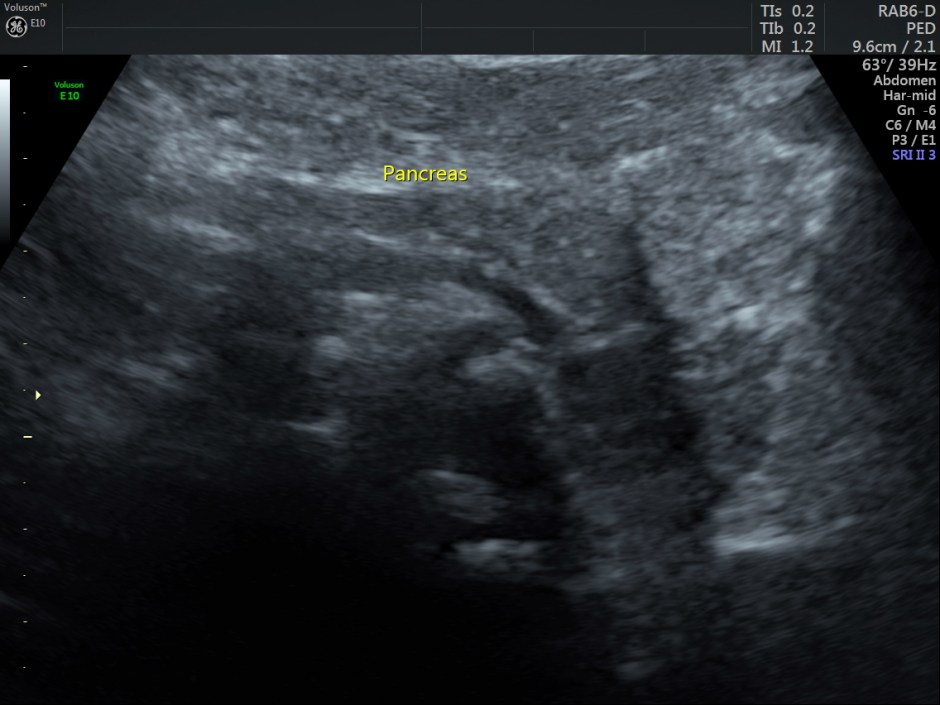

The scan revealed the following findings:

Other laboratory studies may be directed by history, physical examination, peripheral smear, and other laboratory findings. Ultrasonography is used to estimate the spleen size since the physical examination occasionally does not detect significant splenomegaly. Chest radiography, electrocardiography (ECG), and other studies are used to evaluate cardiopulmonary status.